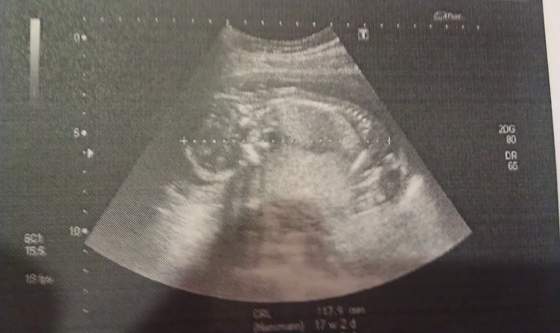

Ja też właśnie wróciłam z usg ;-)

Lekarz bardzo małomówny dziś był ... powiedział tylko na koniec "wygląda na to, że wszystko dobrze", ehh... coraz bardziej utwierdzam się w przekonaniu, żeby wrócić do wizyt prywatnych.

Dzidzia ma już 18 cmważy 196 g o ile dobrze wyczytałam

Zobacz załącznik 595936Zobacz załącznik 595937Zobacz załącznik 595938Zobacz załącznik 595939